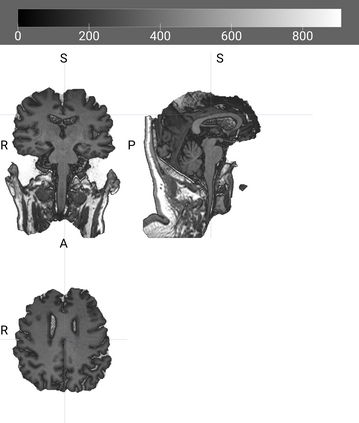

The rapid advancements in machine learning, graphics processing technologies and availability of medical imaging data has led to a rapid increase in use of machine learning models in the medical domain. This was exacerbated by the rapid advancements in convolutional neural network (CNN) based architectures, which were adopted by the medical imaging community to assist clinicians in disease diagnosis. Since the grand success of AlexNet in 2012, CNNs have been increasingly used in medical image analysis to improve the efficiency of human clinicians. In recent years, three-dimensional (3D) CNNs have been employed for analysis of medical images. In this paper, we trace the history of how the 3D CNN was developed from its machine learning roots, brief mathematical description of 3D CNN and the preprocessing steps required for medical images before feeding them to 3D CNNs. We review the significant research in the field of 3D medical imaging analysis using 3D CNNs (and its variants) in different medical areas such as classification, segmentation, detection, and localization. We conclude by discussing the challenges associated with the use of 3D CNNs in the medical imaging domain (and the use of deep learning models, in general) and possible future trends in the field.